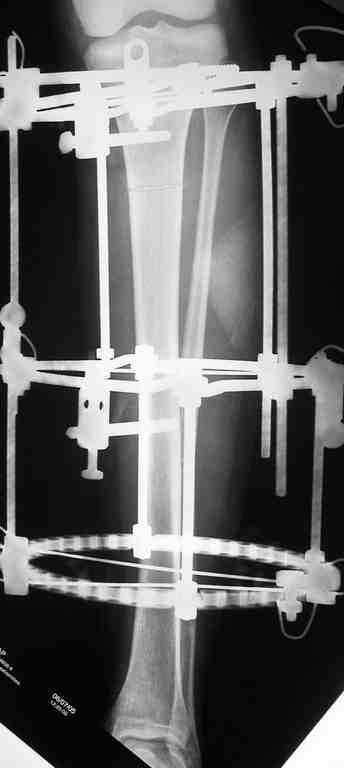

Выше приведены рентгенограммы 13-летнего подростка, страдающего от огнестрельного многооскольчатого перелома дистальной трети бедра. AO наружный фиксатор наложенный в день травмы не дал приемлемой редукции. Через три недели после перелома аппарат Илизарова был наложен без попытки одномоментной репозиции на операционном столе. There are X-Rays of a thirteen year old boy with a comminuted distal femur fracture secondary to a gunshot wound, initially treated with an AO external fixator. The alignment was unacceptable and an Ilizarov external fixator was applied three weeks after the injury. No attempt of definitive reduction was made during the surgery.

Гексаподная приставки наложена на 10 дней и приемлемая редукция была получена. The Hexapod set was applied for ten days and acceptable reduction was received.

По окончанию редукции Гексаподный сет был снят и дальнейшее ведение больного проходило в стандартном режиме аппарата Илизарова. Хороший анатомо-функциональный результат был получен. When reduction was finished, the Hexapod set was removed and further management has been continued by standard Ilizarov regime. Good anatomic and functional results were achieved.